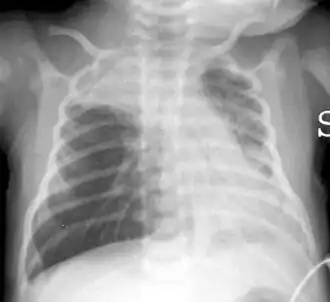

Een thoraxfoto die een hyperinflatie laat zien met een afgevlakt middenrif en bilaterale atelectase in de rechter apicale (longtop) en linker basale (longbasis) regio's bij een 16 dagen oud kind met ernstige bronchiolitis.